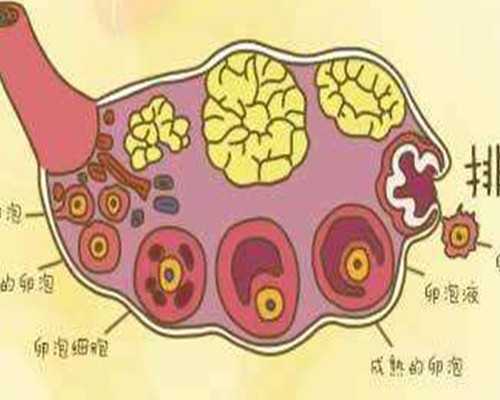

供卵服務的基礎費用通常包括一系列醫療檢查項目,如激素水平檢測、超聲監測和遺傳篩查等,這些檢查確保供體健康和安全。藥物費用占比較大,涉及促排卵藥物的使用,其價格受品牌和劑量影響,波動在數千元到上萬元不等。在公立醫院,這類費用相對規范,常納入醫保部分報銷范圍;而私立機構可能提供更靈活的選項,但需自費承擔。家庭在選擇時,應要求機構提供明細清單,避免隱性收費。